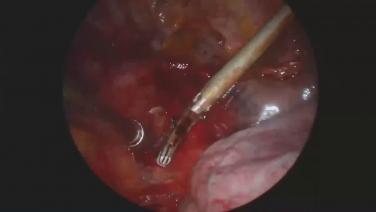

Thoracic Surgery Techniques & Approaches using Ultrasonic Energy with Zane Hammoud, MD

Ultrasonic Energy in VATS with Moishe Liberman, MD

Lobectomy Incision Location with Robert McKenna, MD

Left Lower Lobectomy Instruments with Scott J. Swanson, MD

Right Upper Lobectomy Demonstration with Robert McKenna, MD